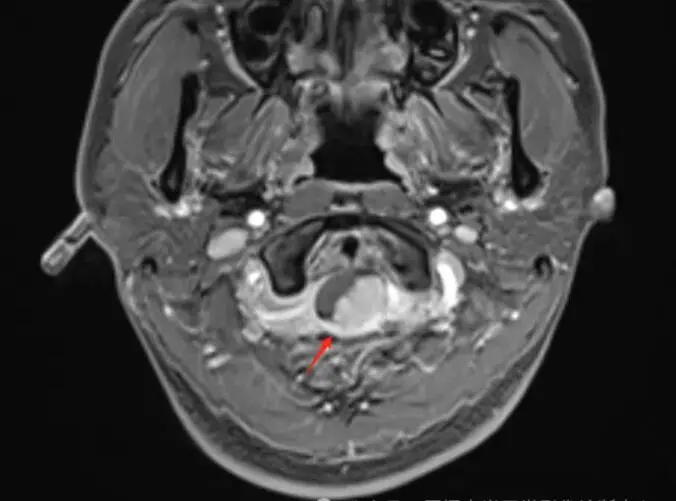

T1压脂增强轴位

检查所见:检查发现其C1椎体-向上枕大孔上部水平椎管髓外硬膜下占位,考虑是脊膜瘤。